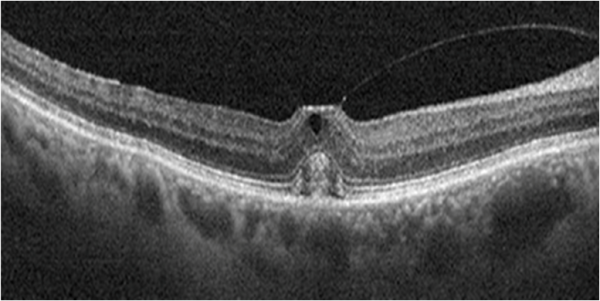

Idiopathic polypoidal choroidal vasculopathy (IPCV)

IPCV is a disease of choroidal vasculature characterized by serosanguinous detachments of the pigmented epithelium and exudative changes that commonly lead to subretinal fibrosis. OCT features of IPCV are multiple PEDs, sharp PED peak, PED notch, and rounded sub-RPE hyporeflective area.

Dome-shaped maculopathy:[31]

It is an anterior convex protrusion of the macula toward the vitreous cavity seen on OCT. It is associated with high myopia and posterior staphyloma.

It exhibits a posterior globe bulge, resulting in a deep concave B-scan OCT and distorted retinal structures.

Focal choroidal excavation[33]

It is defined as an area of concavity in the choroid detected on OCT. These are mostly present in the macular region without evidence of accompanying scleral ectasia or posterior staphyloma.